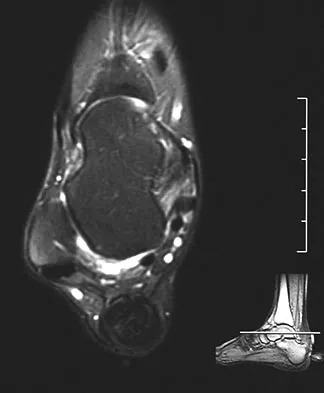

A 25-year-old competitive skier sustains a twisting injury to the right ankle while skiing. She is unable to continue the activity secondary to severe lateral ankle pain. Examination reveals ecchymosis and fullness over the lateral malleolus with pain and weakness on active ankle dorsiflexion and external rotation. There is no medial-sided pain. Neurovascular examination is normal. An AP radiograph and MRI scan are shown in Figures 17a and 17b, respectively. Management should consist of

Explanation